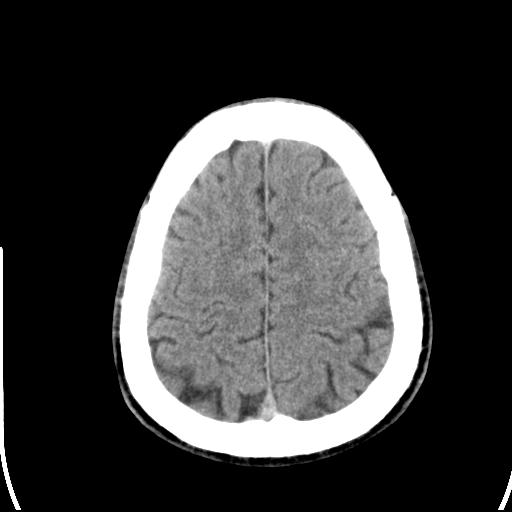

标题: CT25435:头皮下高密度影???

头皮下高密度结节影???临床上在老年男性比较常见。大家看看是什么?成因是? 本例患者,男性,51岁。外伤来诊。无染发史及发根植入史。